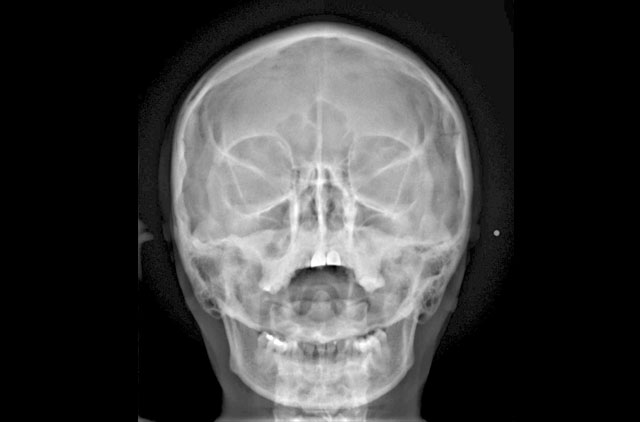

-Anteroposterior (AP)

-Posteroanterior (PA)

-Caldwell